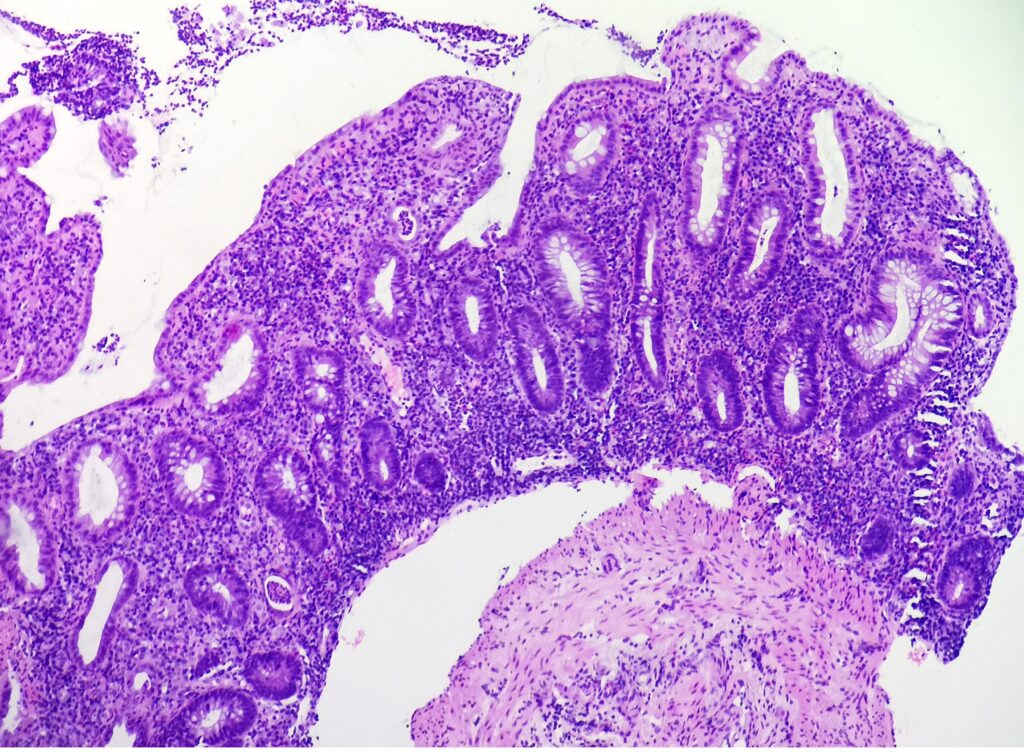

Pacjentka 57 letnia z wieloletnim wywiadem wrzodziejącego zapalenia jelita grubego przyjęta do Poradni Endoskopowej w trakcie klinicznego zaostrzenia objawów. Klinicznie wykluczono odczyny polekowe oraz czynniki infekcyjne. W kolonoskopii w odbytnicy, esicy, zstępnicy i poprzecznicy stwierdzono obrzękniętą, nierówną, wyboistą błonę śluzową z nadżerkami i polipami rzekomymi, krwawiącą kontaktowo. Ze zmienionych obszarów pobrano wycinki.

- zapalenie ograniczone do blaszki właściwej błony śluzowej jelita grubego

- naciek zapalny składający się z limfocytów, plazmocytów (w tym charakterystycznie u podstawy krypt, niebieska strzałka), makrofagów, granulocytów kwasochłonnych i granulocytów obojętnochłonnych

- wnikanie granulocytów obojętnochłonnych do nabłonka powierzchownego i kryptowego, tworzenie ropni kryptowych (granulocyty w świetle krypt, gwiazdka) i nadżerek (zielona strzałka)

- cechy przewlekłego zapalenia – zaburzenie architektoniki krypt – nieregularność, skrócenie, rozgałęziania się, poszerzenie, krypty nie dochodzą do mięśniówki śluzówki i są rozmieszczone w nieregularnych odległościach (żółta strzałka), obecność komórek Panetha (czerwona strzałka)

- w tym przypadku brak dysplazji nabłonka gruczołowego, brak ziarniniaków, nacieku zapalnego przekraczającego mięśniówkę śluzówki, nieobecność charakterystycznych inkluzji wirusowych bądź mikroorganizmów

Wrzodziejące zapalenie jelita grubego, faza zostrzenia – w oparciu o dane klinicze (ulcerative colitis, UC).